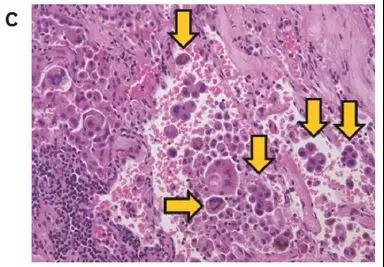

图A,病理检查肿瘤周边没有STAS

图B,病理检查发现肿瘤周边有1-4个癌细胞或癌巢,属于低STAS

图C,病理检查发现肿瘤周边有超过5个癌细胞或癌巢,属于高STAS